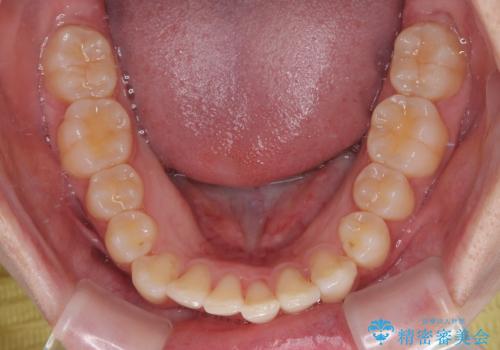

- 上下前歯の重なりを気にして来院された患者様です。

安価なインビザラインパッケージを用いての治療を希望されており、デコボコの程度が中等度であったため、インビザライン・モデレートを用いて矯正治療を行うこととしました。